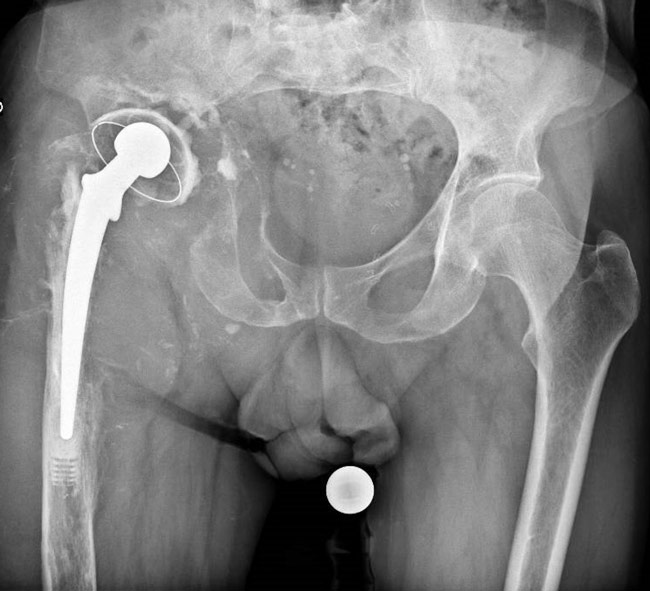

A hip revision with a stemmed cup (transtrochanteric approach for gluts) and Allograft Prosthetic Composites was performed.

A hip revision with a stemmed cup

A Lagrange and Letournel femoral cemented stem was implanted